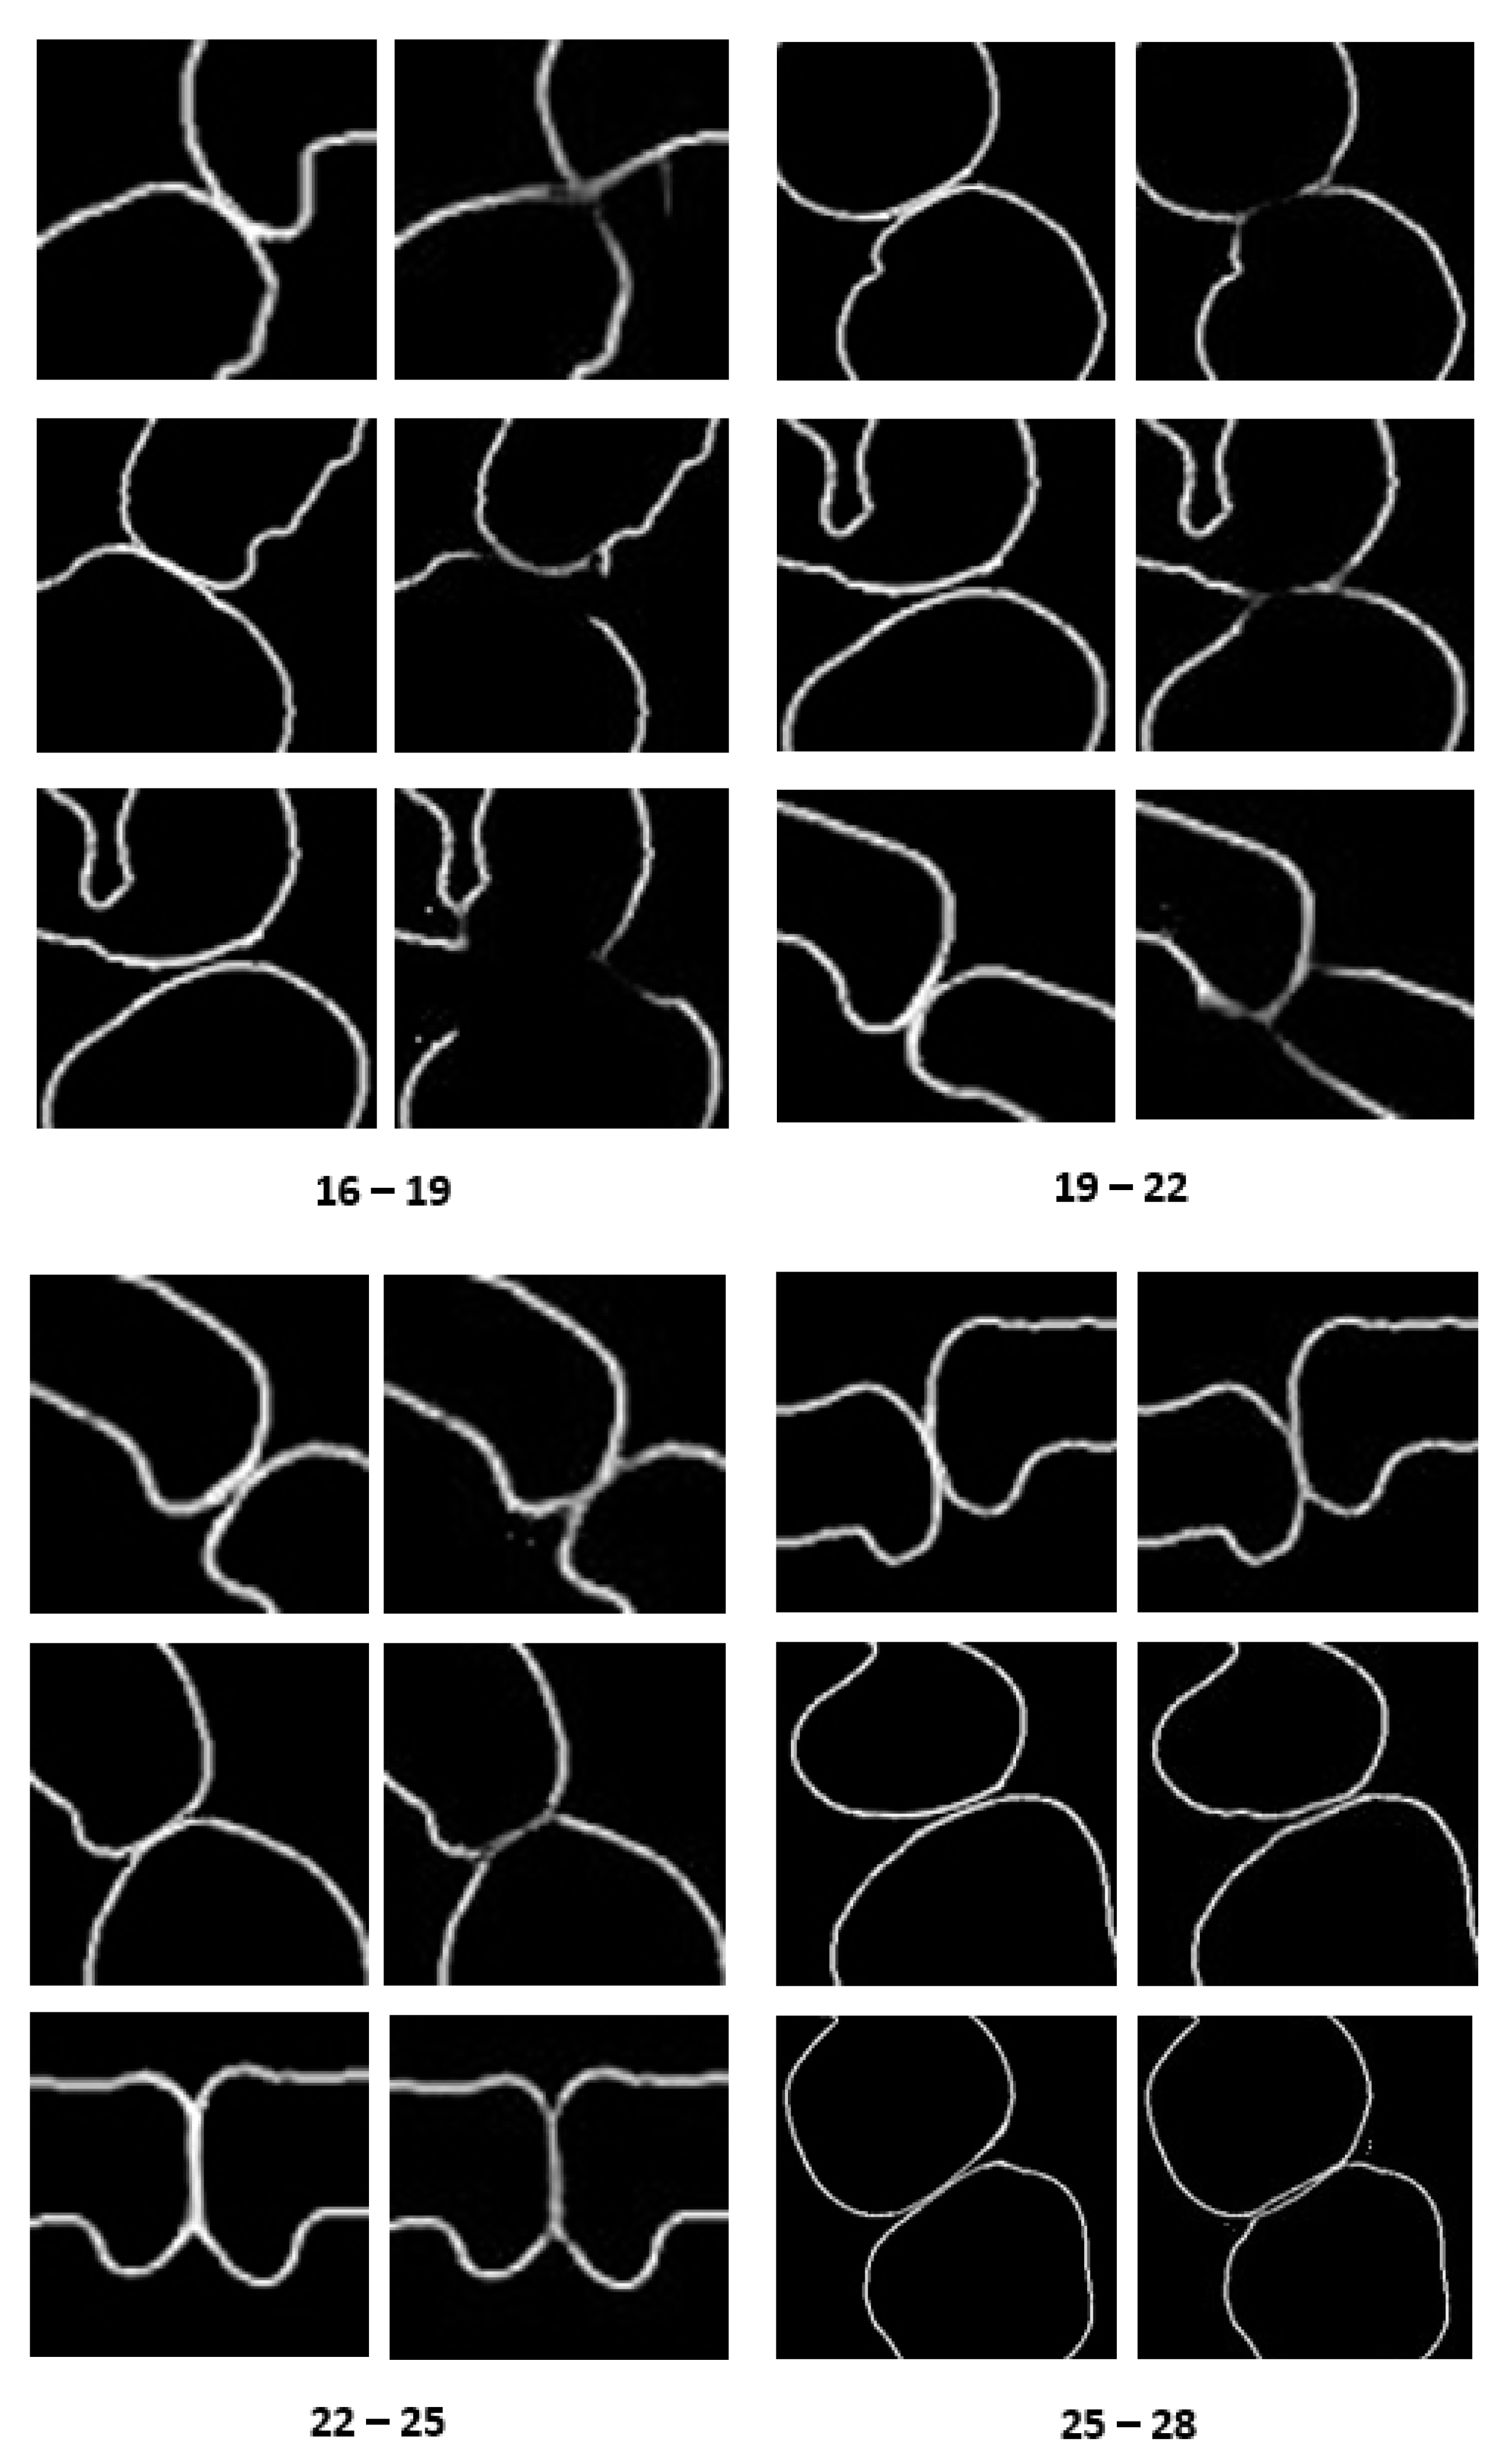

3.2. Results of Tooth Segmentation

3.2.1. Tooth Model